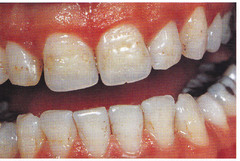

amelogenesis imperfecta on radiograph

Front

Back